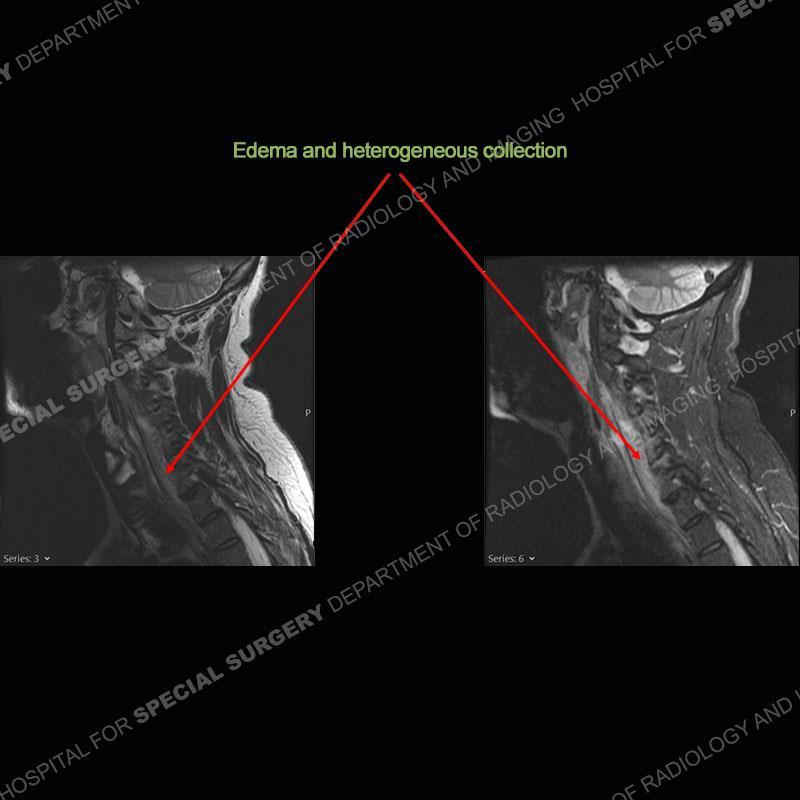

The radiographs demonstrate a prevertebral soft tissue fullness centered at C5-C6 that persists even on extension. There is a slight loss of disc height at C5-C6. The CT more readily shows the prevertebral soft tissue swelling at C5C6 where there is a punctate focus of gas. On the MRI, there is a marked amount of edema and a heterogeneous collection in the prevertebral soft tissue at C5-C6. Edema is present of the C5 and C6 vertebral bodies with a loss of the normal architecture about the disc space. A heterogeneous epidural collection has formed that causes compression of the spinal cord asymmetric to the left side and also precipitates severe left sided neural foraminal stenosis.